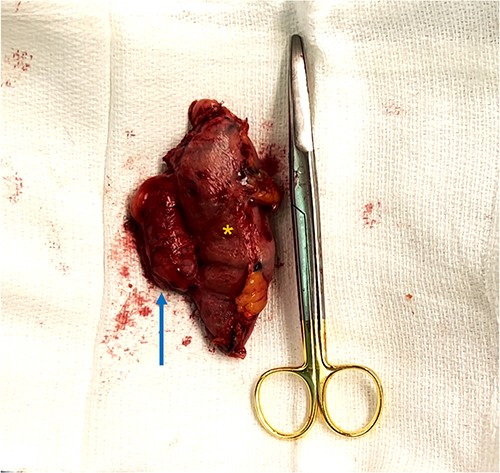

An intra-operative EGD was performed to assist with localizing the GGF and demonstrated a wide-mouthed fistula ~2 cm proximal to a widely patent GJ without an associated marginal ulcer. Purple cartridges on the Signia staple gun were then used to divide the remnant stomach at the level of the mid-body as well as the lateral aspect of the gastric pouch. Extreme care was taken to ensure the GJ and roux limb were preserved and not injured during this step. The en-bloc GGF specimen was removed and inspected on the back table demonstrating the fistulous connection between the remnant stomach and gastric pouch, ensuring a complete resection of the fistula (Figs 4 and 5). The total operative time was 1 h and 21 min.

En-bloc resection of gastrogastric fistula with excised portions of gastric pouch (arrow) and gastric remnant (asterisks).

Scissors placed through gastrogastric fistula demonstrating complete resection of fistula.